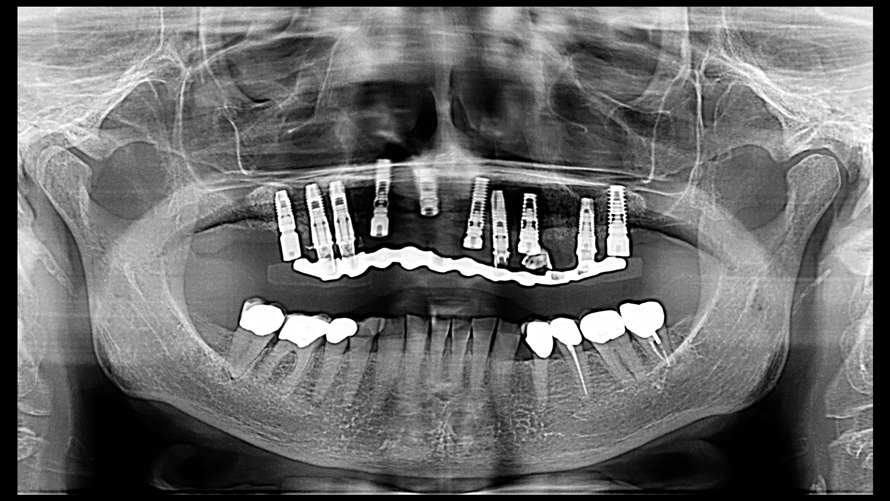

(16.) Photograph of failing implant prosthetics that may require specialty care taken with a smartphone and an EALS device.

Figure 16

(17.) Photograph of failing implant prosthetics that may require specialty care taken with a smartphone and an EALS device.

Figure 17